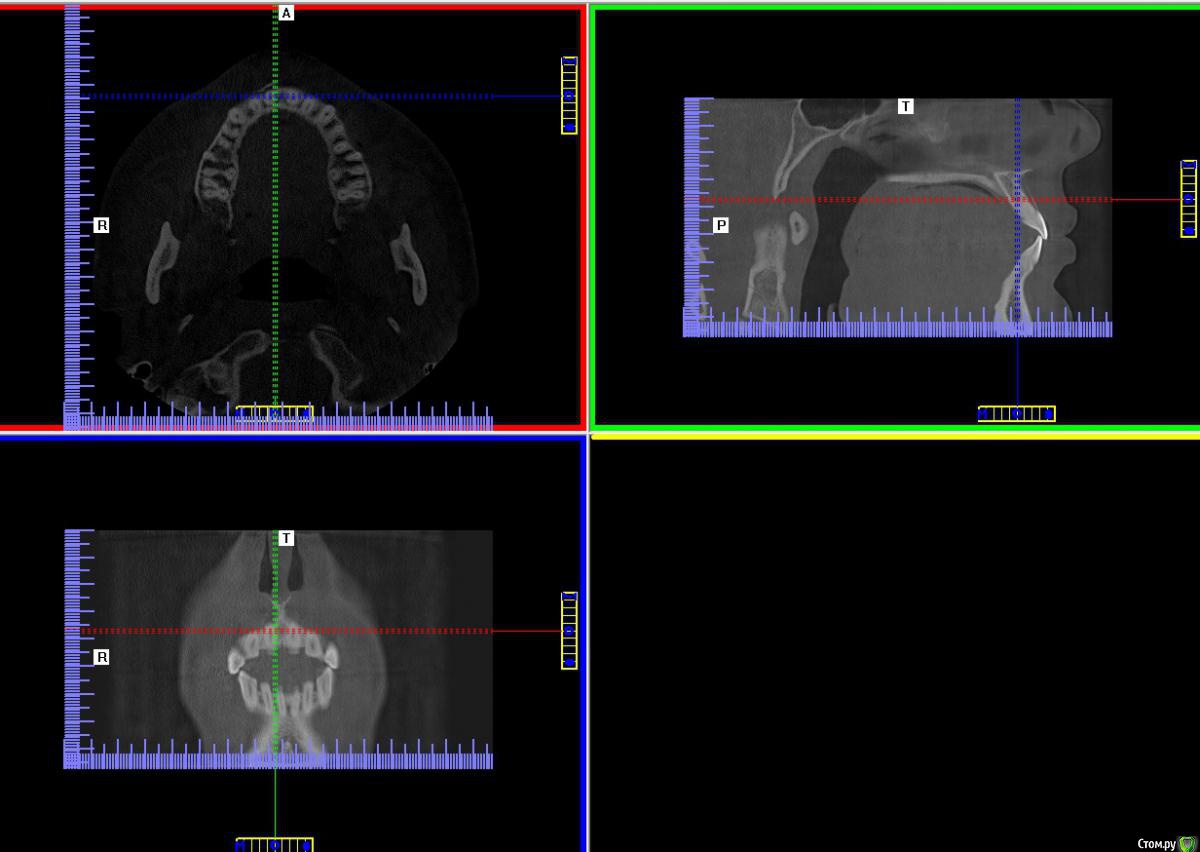

Александр К Опубликовано 8 февраля, 2016 Поделиться Опубликовано 8 февраля, 2016 Добрый день! С супругой произошла неприятность, подскользнулась, получила травму - удар в область передних верхних зубов. Удар был не сильный, даже ни опухоли, ни синяка, ни разбитой губы, но... Шатаеся один зуб уже неделю, чуть болит. После похода в гос и частную клинику совершенно разные вердикты, причем в частной вообще жуть: по томографии врач сказал, что откололась часть кости к которой крепится зуб и теперь его надо удалять, вшивать "новую" кость, ходить пять дней без зуба, потом пол года с элементом вставной челюсти, потом вставлять корень и новый зуб. Все бы ничего, но зуб то вроде целый и для девочки это все ой как не приятно и сложно, да и дорого что тут греха таить.Загуглив я сделал вывод что это перелом альвеолярного отростка верхней челюсти, пишут что установкой шины можно это вылечить. Жалко вот так вот терять здоровый зуб.Теперь о гос поликлинике: врач сделала рентген и указала на перелом корня, хотя врач из частной клиники перелома не увидел. В общем кому верить и что делать не знаем. Пойдем к третьему врачу, но хотелось бы послушать мнение профессионалов со стороны. Буду благодарен любому ответу, спасибо! Ссылка на комментарий

Александр К Опубликовано 9 февраля, 2016 Автор Поделиться Опубликовано 9 февраля, 2016 Скиньте ссылку на КТ, посмотрюhttps://cloud.mail.ru/public/Jvbk/gvPpoBJrQСпасибо Ссылка на комментарий